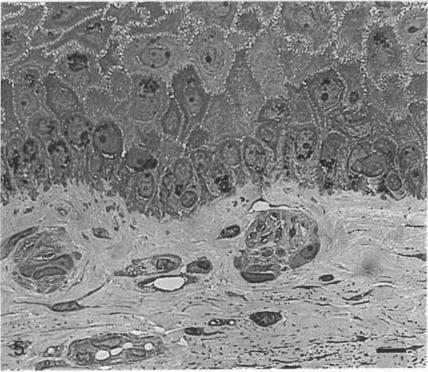

Corpuscular nerve endings were found to be numerous within a narrow, 1.00 mm wide, annular zone of limbal conjunctiva, located approximately 0.5 mm from the corneoscleral margin. A light and electron microscopic study was carried out on these nerve endings found within samples of human eye-bank material. Corpuscular endings were found immediately under the epithelium, often within the stromal elevations which make up the limbal palisades of Vogt. They were round to oval in shape, and varied in size, with a mean maximum diameter of 30 microns. The afferent nerve fibre lost its myelin sheath soon after entry, and subsequently branched to give rise to a variable number of axon terminal varicosities, which were characterised by an accumulation of mitochondria. Neural elements within the nerve ending were invested by the cytoplasmic lamellae of Schwann-like accessory cells. The corpuscle was demarcated from the surrounding connective tissue by a delicate fibrocyte capsule. The corpuscular nerve endings described here in the conjunctiva share features common to corpuscles found in other mucosae. The function of such complex sensory nerve endings is as yet unknown, but the possibility that they represent receptors for particular sensory modalities should be explored.